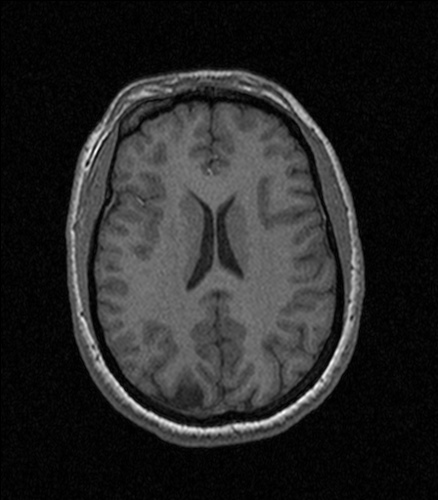

A new study that matches words with brain activity patterns could help neuroscientists understand how people think about abstract, complex concepts, researchers say. It lends a physiological definition to the concept of higher thinking, using functional magnetic resonance imaging and a computer program that condensed 3,500 Wikipedia articles.

Researchers at Princeton University looked at fMRI scans to identify brain regions that were activated when participants thought about certain objects, like a carrot or a house. Then the team generated a list of topics that were also associated with those words. They looked at the same fMRI scans to determine the brain activity that was shared by the words within each topic, as a Princeton news release puts it. For instance, thoughts about the idea of “furniture” shared similar patterns with words like “table,” “desk” and “chair.”

Once they could tell the fMRI activity that would be sparked by a particular topic, the researchers were able to look at the brain activity alone and extrapolate what the person was thinking about. If a scientist studying brain scans spotted the neural patterns corresponding to “chair,” he could tell that the person was thinking about furniture.

The researchers started out with brain scans from a 2008 word association study, in which participants were shown a picture and a word of five objects in 12 categories. The participants had been asked to visualize the object for three seconds, and the fMRI recorded their neural activity. Then the Princeton researchers came up with a list of their own topics with which to characterize this fMRI data. They used a computer program to condense 3,500 Wikipedia articles about objects — like an airplane, heroin, birds and manual transmission. The program came up with 40 topics to which these things could relate — i.e. aviation, drugs, animals or machinery. (Their full paper is available online for those interested in the specific methods.)

They arranged the fMRI scans by subject matter, and were ultimately able to tell the general topic on a person’s mind. It was harder to pick out an individual object, however, the Princeton news office explains. The eventual goal is to translate brain activity patterns into the correct words to fully describe thoughts, the researchers say.